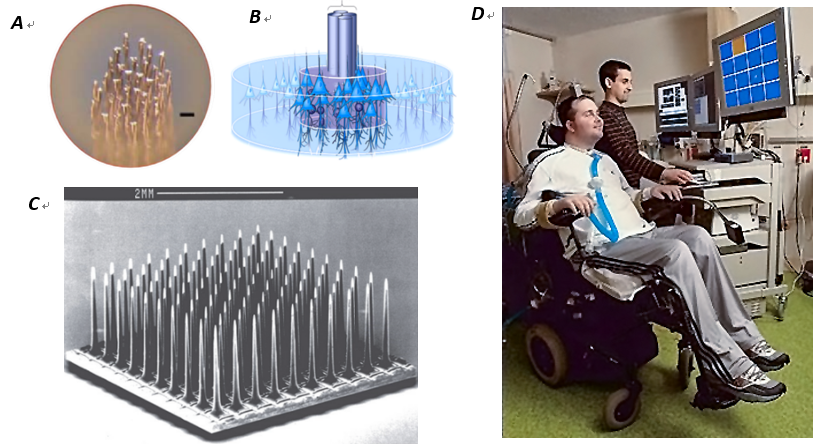

微线电极(Microwire electrodes)

微线电极是一种历史悠久的用于电生理学研究的微电极,它的使用可以追溯到20世纪40年代。[9]微线电极的中心是一根导电金属线芯,周围由耐电解质溶液的绝缘材料(如聚合物、陶瓷或玻璃)包覆,只露出微小的金属尖端。(Fig1.A)玻璃包覆钨微丝的电极可以使用简单的工具拉制,其尖端可达到与脑皮层中神经元的胞体大小相当。使用这种电极曾首次记录到了靠近放电神经元胞体的细胞外神经活动信号,并且达到了高信噪比。基于这种电极的神经记录技术在神经科学研究史中做出了大量重要贡献,在初级视皮层、海马体、颞下皮层等脑区,针对感觉、知觉和运动控制的神经关联方面都进行了开创性的研究。[10-13]慢性植入记录实验表明,直径小于20µm的微线电极可以显著降低脑组织对插入微丝的排异反应。

四极电极是一种由四根电极组成的四通道束型微线电极小阵列。四极电极可以将来自同一信源的神经元电信号由空间位置略微不同的4个电极点同时检测到。(图1.B)这种电极小阵列中每个电极金属触点的直径通常小于30μm。[14]四极电极与单通道电极相比的主要优点是,由于四电极的每个电极与神经元之间的空间距离不同,四个电极检测到的细胞外电位波形就不同。[15]使用聚类方法对细胞外电位信号进行分类就能分离出相邻神经元各自发出的脉冲。[16]

犹他阵列(Utah array)

犹他阵列是一种已经商业化的用于脑皮层内植入的电极阵列,采用了平面外加工工艺。犹他阵列由约100根硅针形电极构成,硅针间距400μm,导电尖端暴露直径10-30μm。(Fig1.C)该阵列采用MEMS技术经过化学微加工、金属沉积和聚合物封装制成。[17]神经科学家需要对脑内神经电信号进行长期稳定的慢性记录并提出了将整个电极阵列封闭在颅骨内的想法。Utah阵列的设计方案正是解决了带支撑底板和引线的平面刺入式电极阵列植入脑皮层后关闭颅骨的问题。由于犹他阵列具有通道数较多,对脑皮层的覆盖面积和电极密度较均衡,并且适合慢性记录的特点,它主要用在大型动物,特别是非人类的脑神经信号记录中。但由于硅针电极较短(一般不超过1.5mm),它比较适合记录脑皮层的神经信号。犹他电极与微线电极的相似之处在每根针上只有尖端有一个电极触点。将密集阵列中近百个探针同时插入皮层中的难度较大,需要借助专用的微型气锤才能将其植入。[16, 18, 19]

犹他阵列及配套的记录系统已经被美国食品和药物管理局(FDA)批准用于皮层内信号脑机接口技术(iBMI)的临床研究。犹他阵列目前主要用在运动脑机接口临床试验中,该实验通过将运动相关的神经信号从大脑传递到外部效应器,替换和恢复瘫痪患者受损伤的运动功能。(Fig1.D)主要的方法是在患者大脑中负责肢体运动的脑皮层区域植入单个或多(两)个犹他阵列。目前在非人灵长类实验中实现了在同一只猕猴的视皮层同时植入总数超过500个通道的多个犹他阵列。[20]

Fig 1: A. thefeature of microwire electrodes array; B. the illustration of tetrode in neuraltissue; C. Utah array; D. the clinical investigation of intracorticalbrain-machine interface.